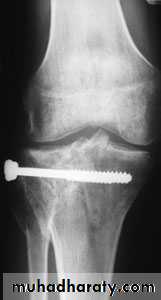

Undisplaced fractures treated conservatively: Haemarthrosis aspiration and compression bandaging,above knee cast for one months followed by functional brace and physiotherapy.For displaced fractures treatment is by open reduction and internal fixation with plate and screws as it is an intra articular fracture.

fixation of tibial plateau fracture